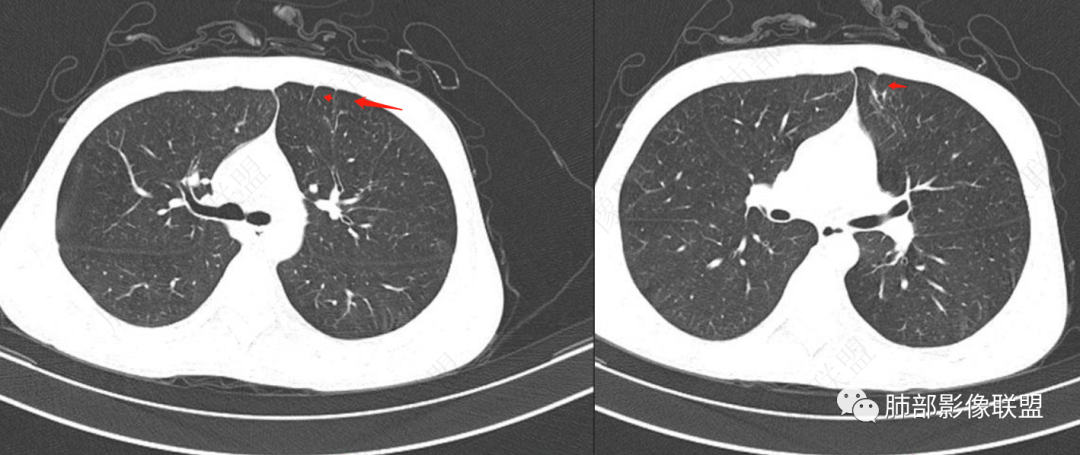

青年女性,干细胞移植后出现憋喘胸闷气短,术前和术后CT可见支气管进行性扩张,双肺野淡磨玻璃影,考虑移植后抗宿主病,闭塞性细支气管炎(BO)。

青年女性,移植术后,支气管管壁略增厚,进行性扩张,多发小结节,考虑闭塞性支气管炎,跟大家学习

这个主要是临床,影像比较单一,有纵隔气肿;两侧对比:后者确实肺密度减低,体积增大,有气体潴留的特点

支持小气道病变:  闭塞性细支气管炎